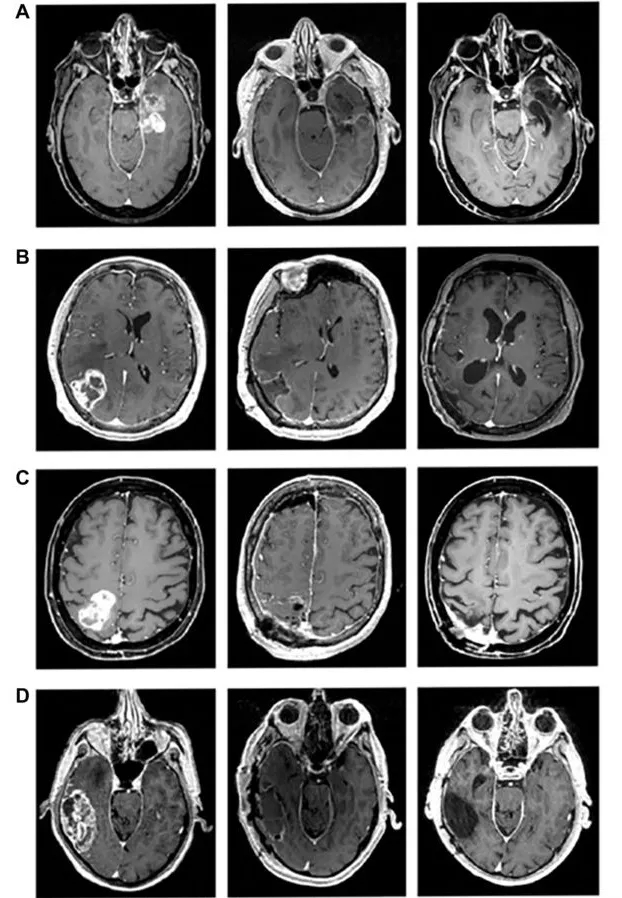

此外,放射影像结果为疗效提供了直观佐证:

1、全切除术患者(详见下图A-D):切除部位持续无解剖强化,MRI扫描显示,术前、术后及试验结束时均无异常强化信号;4例患者最新随访时间分别为31个月(图A)、35个月(图B)、44个月(图C)、24个月(图D)。

▲图源“Clin Cancer Res”,版权归原作者所有,如无意中侵犯了知识产权,请联系我们删除

2、次全切除术患者(详见下图E-H):肿瘤体积呈现“先增后减”特征,术后6个月内开始持续缩小,符合“真性假性进展”判定——这是免疫治疗特有的良性表现,本质是激活的免疫细胞聚集引发局部炎症水肿,而非肿瘤增殖,恰恰提示免疫疗法正在发挥作用;4例患者最新随访时间分别为39个月(图E)、51个月(图F)、29个月(图G)、24个月(图H)。